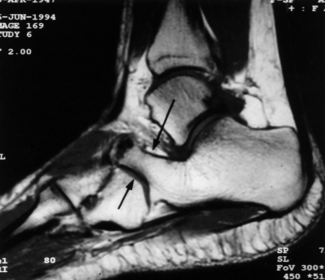

| What is this? What is shown by A and B? | STJ coalition A = talar neck spurring B = Halo or 'C' sign |

| What is this? | Posterior talocalcaneal coalition |